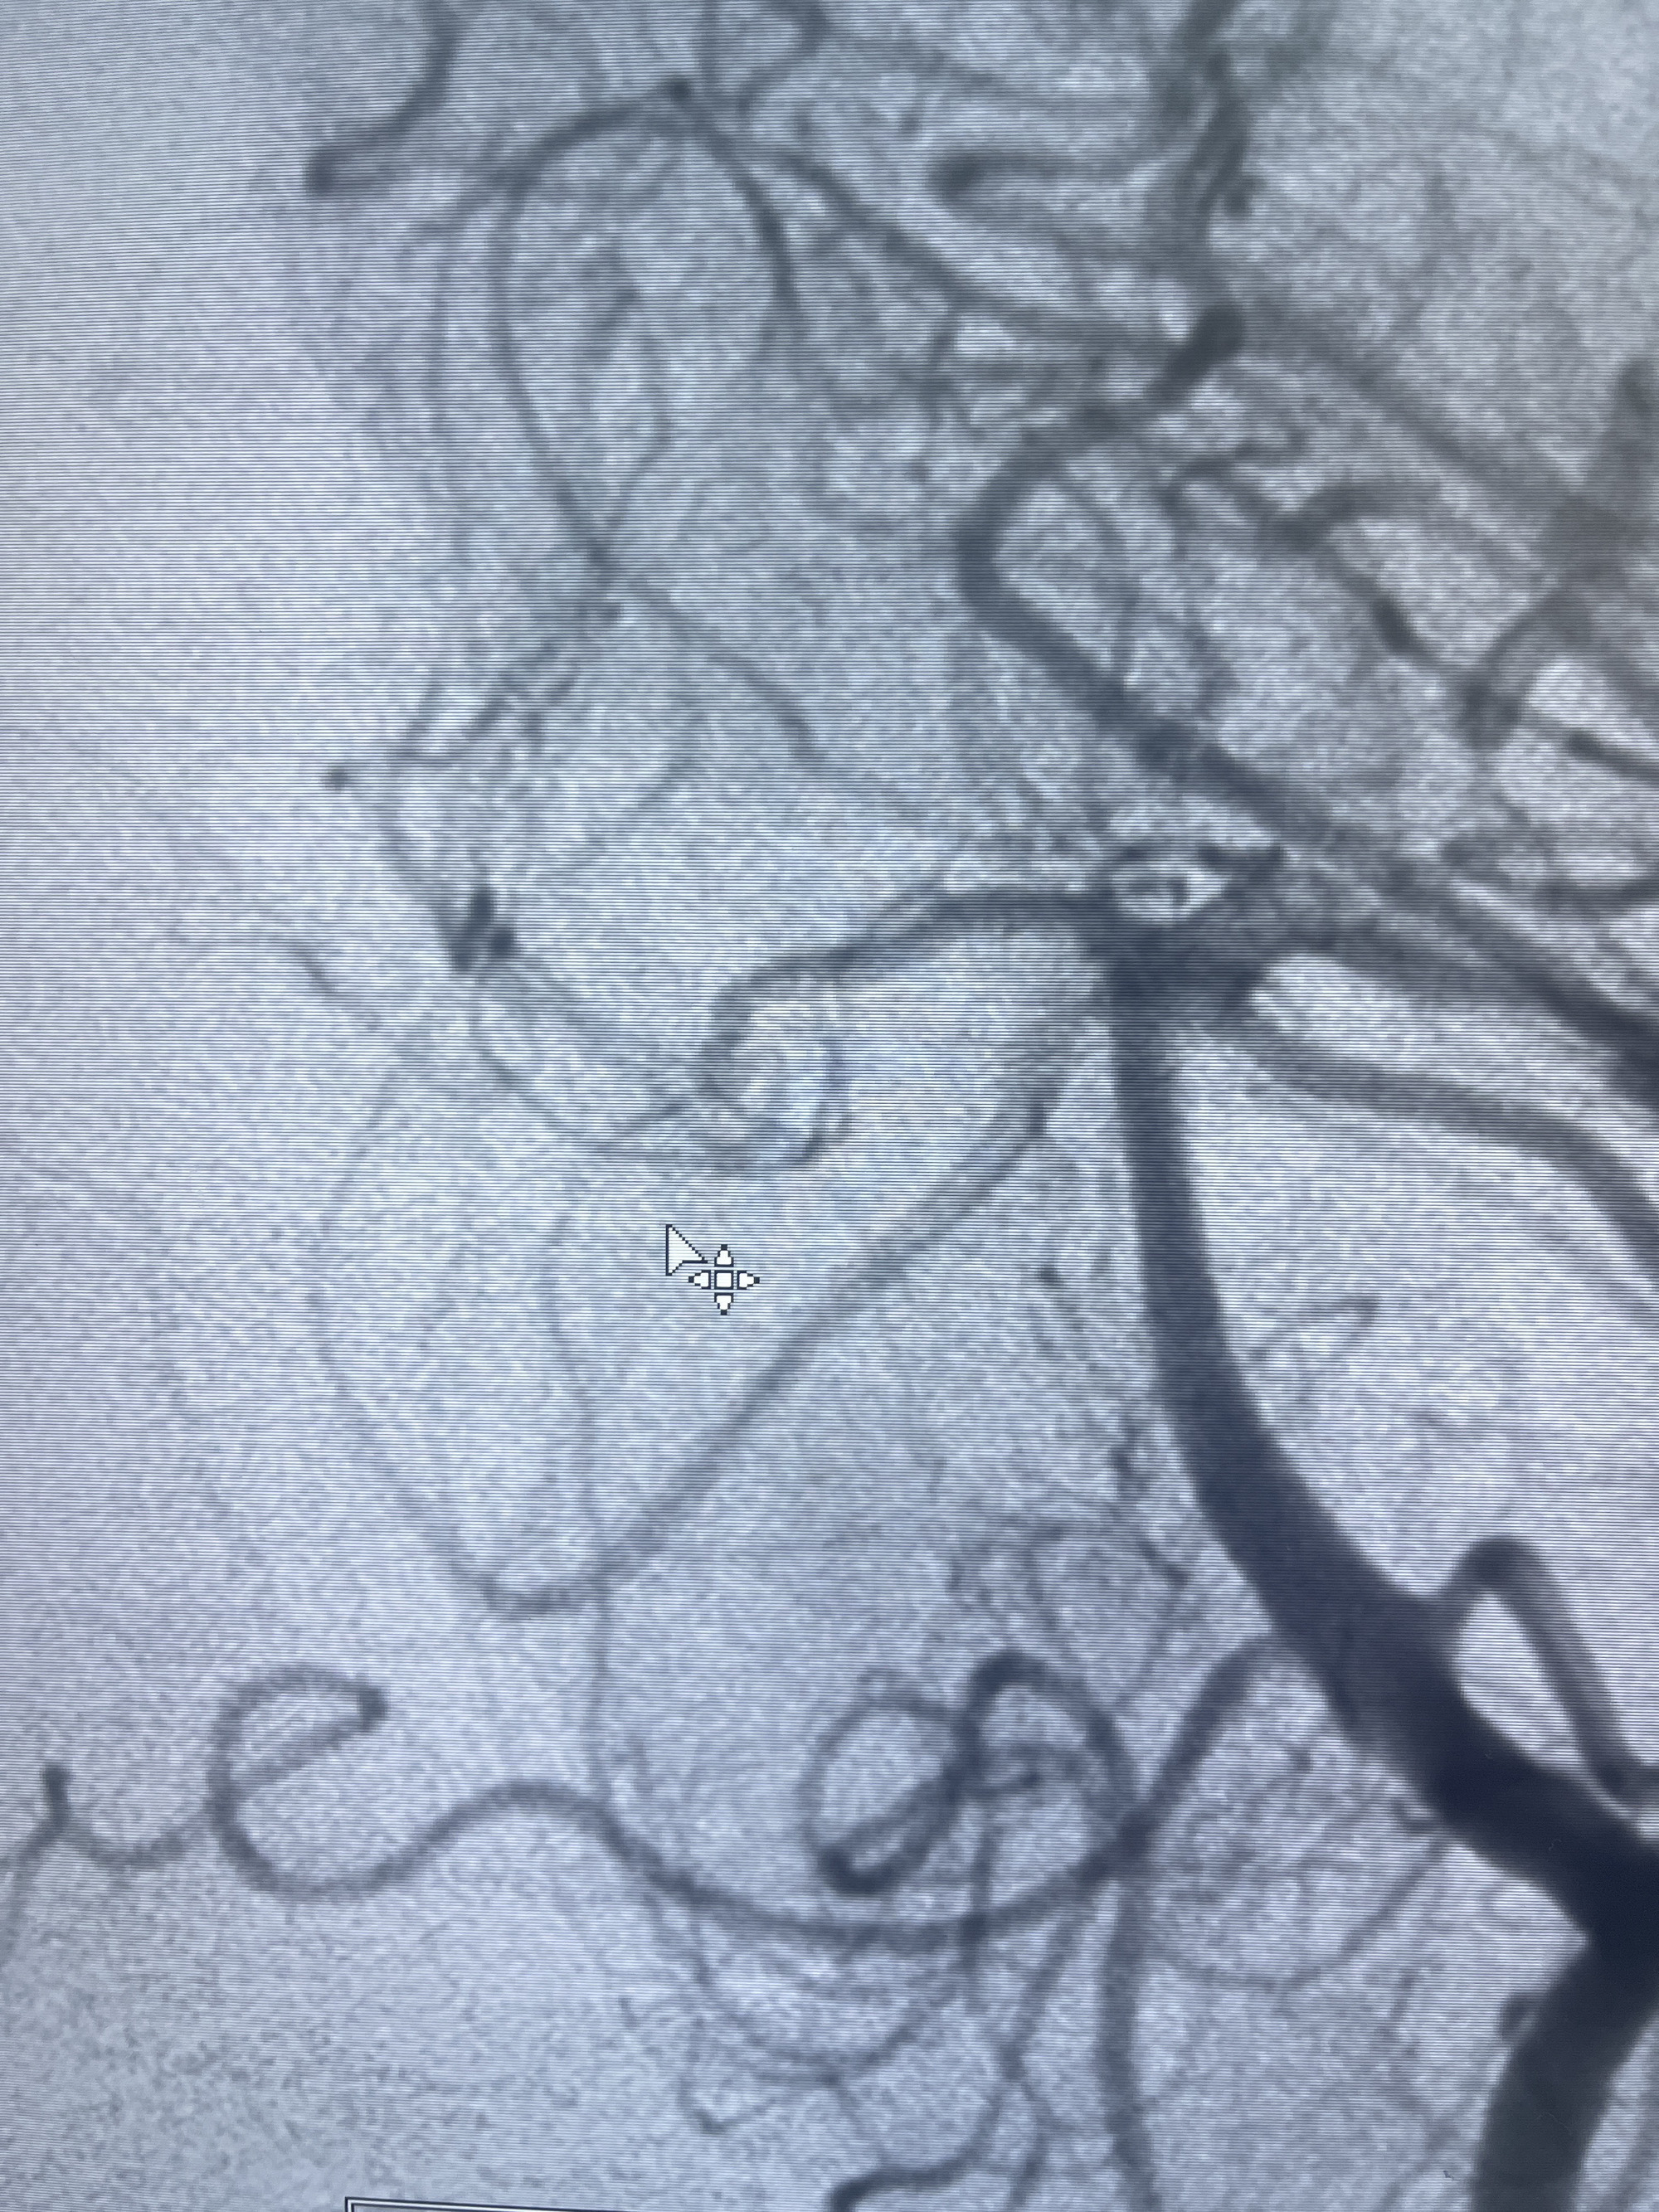

202.04.28脑血管造影:右侧大脑后动脉远段闭塞,右侧椎动脉V4段可见“囊状造影剂填充影”,大小7.64*7.65mm,可见PICA由动脉瘤发出;

1.普通支架辅助弹簧圈栓塞?

2.密网支架辅助弹簧圈栓塞?